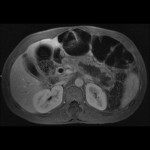

- T1 Post